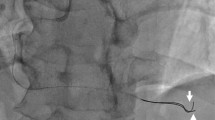

The start points of the systolic phase in the pressure waveform and the Q point in the IC-ECG were regarded as the same point, and the time-phases were synchronized. The IC-ECG-triggered Pd/Pa ratio (ICE-T) value was defined as the average of the Pd/Pa ratio in the period corresponding to the isoelectric line (Fig. 1).

Calculation method for the intracoronary electrocardiogram-based pressure index. (A) The R wave was automatically detected and the cardiac cycle was identified. The slope of the intracoronary electrocardiogram, which was < 1 mV/mSec between T and P waves, was labeled as the isoelectric line. (B) First, the Q point of the intracoronary electrocardiogram (IC-ECG) was synchronized with the start points of the systolic phase in the pressure waveform. The IC-ECG-triggered distal/aortic pressure (Pd/Pa) ratio was defined as the average of Pd/Pa in the period corresponding to the isoelectric line.

An example of the flow and resistance waveform and the IC-ECG recorded in the LAD artery under ATP-induced hyperemia is shown in Fig. 3. Although the isoelectric phase of the IC-ECG waveform was short, the isoelectric line of the IC-ECG was caught just after the peak flow velocity. The flow velocity varied markedly during the WFP compared with the ICE-T analysis period.

An example of flow velocity, resistance, and intracoronary electrocardiogram recorded in the left anterior descending coronary artery under hyperemia. The flow velocity decreased sharply after reaching a high peak flow. The isoelectric line of the intracoronary electrocardiogram detected the phase immediately after the peak flow velocity. The flow velocity varied greatly during the WFP.